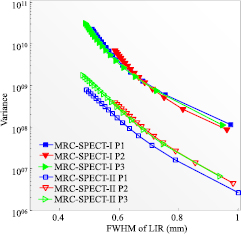

Compared with MRC-SPECT-I (figures 7 and 8), the image variance obtained with the MRC-SPECT-II system (MRC-SPECT-II-C) at the center of FOV was more than 20 times lower when the target spatial resolution was in the range between 0.5 mm and 1 mm. The non-uniformity of MRC-SPECT-II's sensitivity led to appreciable difference in the resolution-variance trade-offs for different spatial locations. As shown in figure 8, the variance increased by 50% when it was moved away from the center by 3.2 mm. Nevertheless, the MRC-SPECT-II system consistently allowed for a reduction in imaging variance by an order of magnitude at a given spatial resolution, when compared to the MRC-SPECT-I system.

Figure 8. Resolution-variance trade-off curves at different locations. P1 is at the FOV center, P2 and P3 are 3.2 mm away from the FOV center in the transverse and axial direction respectively; the same simulated data sets of MRC-SPECT-I and MRC-SPECT-II-C were used as the ones in figure 7.